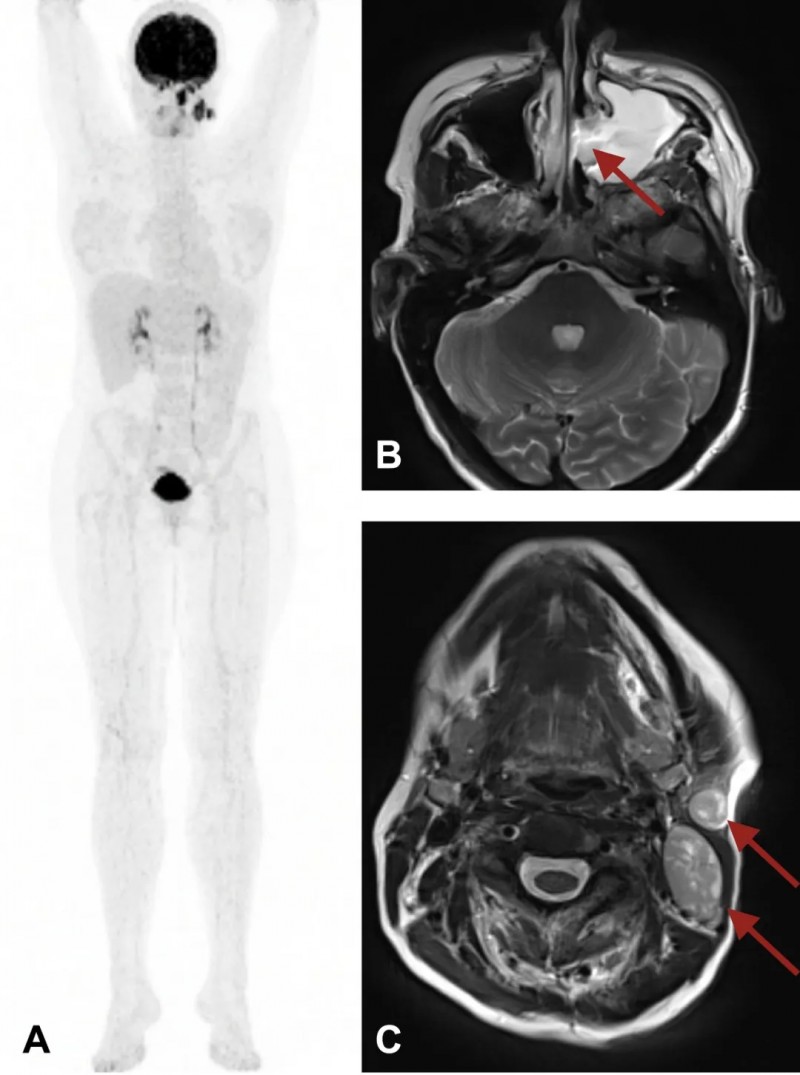

结果显示:治疗前(基线时),患者存在3处肿瘤病变:左鼻腔原发性肿瘤、左侧颈部淋巴结两处转移瘤(详见下图)。其中1处淋巴结转移瘤于治疗第5天切除,用于TIL培养,组织学分析确诊为恶性黑色素瘤转移。

▼该患者治疗前影像图

▲图源“ESMO”,版权归原作者所有,如无意中侵犯了知识产权,请联系我们删除

注:

①图A:PET扫描显示:左鼻腔及左侧颈部淋巴结有3个PET阳性病变;

②图B:MR扫描T2加权显示:原发性肿瘤阻塞左鼻腔;

③图C:MR扫描T2加权显示:左侧颈部两个淋巴结转移。